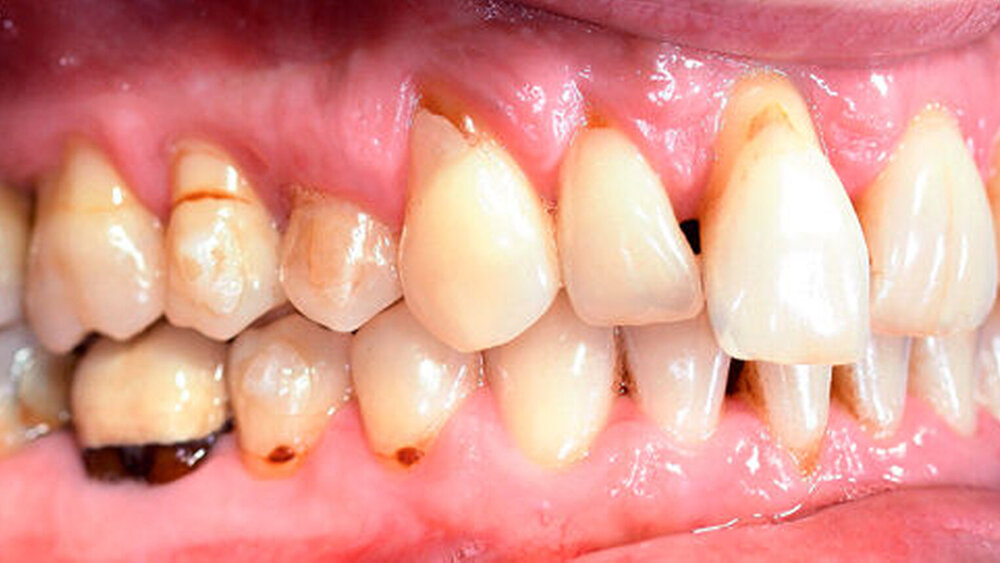

Anamnestisch lagen keine Besonderheiten vor. Es ist jedoch zu vermerken, dass ein regelmäßiger Alkohol-, Koffein- und Nikotinkonsum zugrunde lag. Intraoral zeigte sich ein bereits konservierend versorgtes permanentes Gebiss mit aktivem und inaktivem kariösen Geschehen. Große Anteile der Zahnhälse lagen nach Zahnfleischrückgang in Kombination mit Knocheneinbrüchen frei. Zahn 27 wurde bereits extrahiert.

Eine Beurteilung der parodontalen Situation an Zahn 11 offenbarte mesial und distal Sondierungstiefen von jeweils 6 mm.

Kieferorthopädisch imponierte beidseits eine neutrale Verzahnung bei einem tiefen Biss von 5 mm – bedingt durch die Verlängerung beider Frontzahngruppen. Besonders Zahn 11 zeigte eine erhebliche Verlängerung und Protrusion mit einer sagittalen Frontzahnstufe von 5 mm. Sowohl die Frontzähne im Ober- als auch im Unterkiefer wiesen eine lückige Beziehung zueinander auf (Abbildung 1).